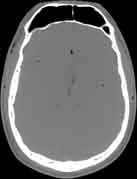

Visible Human male: Sectio transversalis 1080

CT

NMR

Pd T1 T2